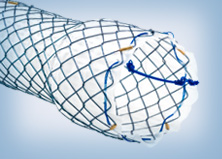

HANAROSTENT Fully Covered Esophageal Stent

To open the stricture, an 18 mm x 80 mm fully covered esophageal HANAROSTENT was introduced. The accurate placement of SEMS in the proximal esophagus is usually challenging.

However, the three marks at the HANAROSTENT’s distal, medial and proximal ends were easily seen under fluoroscopic guidance, and were valuable in ensuring acurate deployment, just distal to the upper esophageal sphincter (Figure 5). The distal end of the HANAROSTENT remained in the patent portion of the previous stent. The endoscopic view of the SEMS proximal end can be observed in the images below (Figures 6, 7 and 8).

Both deployment and patency of the fully covered esophageal HANAROSTENT were very good. The flexibility and softness of the SEMS contributed to the patient’s ability to tolerate a stent placed in the proximal esophagus.

About HANAROSTENT

The 510(k)-cleared HANAROSTENT® Esophagus is made by M.I.Tech and distributed exclusively through Olympus in the U.S. and EU market. The stent is designed to allow for appropriate radial and axial force, reduce the risk of migration, and provide accurate placement. The device is available in 8 sizes to meet an array of therapeutic requirements.